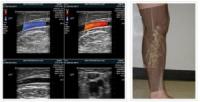

¡®°Ü¿ïö ƯÈ÷ Á¶½É¡¯ ÇÏÁöÁ¤¸Æ·ù, Á¦´ë·Î Ä¡·áÇÏ·Á¸é?

¡ã»çÁø=¹ÎÆ®¿µ»óÀÇÇаú[¿Óóµ¥Àϸ®] ÇÑÆÄ°¡ ÀýÁ¤ÀÌ´Ù. ¿µÇÏ 10µµ...